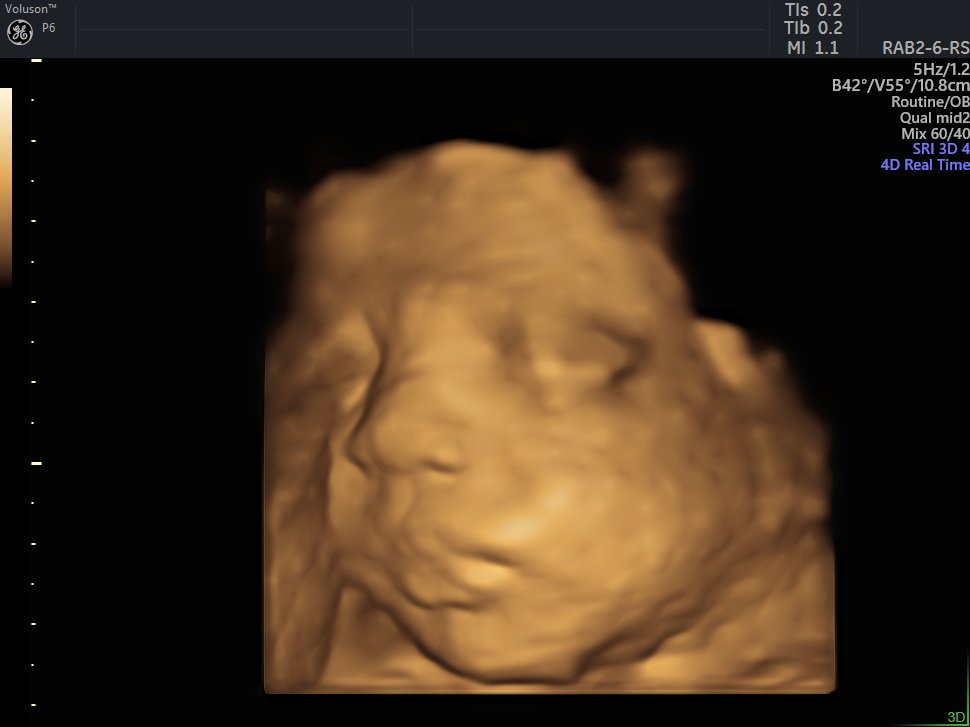

4 Boyutlu (Renkli) Ultrason ve Doppler Ultrasonografi

4 D Ultrasonografi